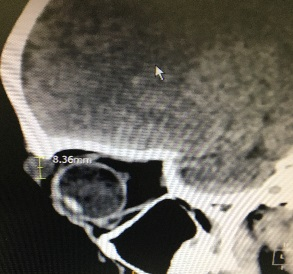

Orbital Tumour Surgery

Any tumour mass can occur within the bony socket of the eye. It may occur as a primary tumour or secondary tumour (metastatic disease). It is also essential to know the difference between a benign and malignant tumour. After discussing the symptoms and signs, a detailed clinical examination and some clinical tests, Dr Nazila will order for an imaging such as CT scan or MRI and advise for surgery.